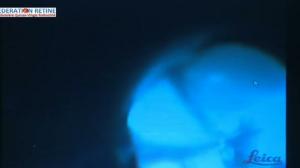

Endorésection tumorale compliquée

Par : Dr Nathalie CASSOUX - Pitié-Salepétrière (Paris-France)

Chaîne : Chirurgie vitréo-rétinienne